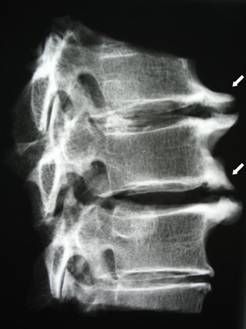

Еще одним заболеванием, при котором может хрустеть шея, является спондилез. Так называется разрастание костной ткани на позвонках. При этом происходит деформация хрящевой ткани, в ней начинают образовываться трещины, разрывы, а в дальнейшем образуется грыжа. Костные выросты (остеофиты) сужают просвет спинномозгового канала, сдавливая тем самым спинной мозг и нервные корешки, отходящие от него.

Заболевание проявляется болями в области шеи и лопаток. Наклоны и повороты головы сопровождаются хрустом и болью. По мере того как процесс прогрессирует, к симптомам присоединяются шум в ушах, головокружения и головные боли, снижение зрения. Спондилез является хроническим заболеванием и, как правило, встречается у людей старше пятидесяти лет.

Кроме этого, для выявления полной картины потребуется рентгенография в нескольких проекциях шейного отдела, компьютерная томография или МРТ. После проведения полного обследования назначается адекватная терапия.

Спондилез

При развитии заболевания на позвонках постепенно образуются остеофиты – дегенеративные выросты. Они цепляют нервные волокна, причиняя серьезную боль.

Основная причина спондилеза – возрастные изменения, вызывающие изменения в метаболизме. Им болеют преимущественно пожилые люди. Однако хруст в шейном отделе позвоночника, причиной которого является спондилез, может появиться и в более молодом возрасте. Способствуют его развитию:

- рентгенография шейного отдела. Обычно снимок делается с двух ракурсов;